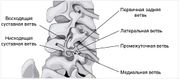

| 13:45, 14 августа 2017 | Bol spina3.jpg (файл) | 18 КБ | Иннервация межпозвоночных суставов | 1 | |